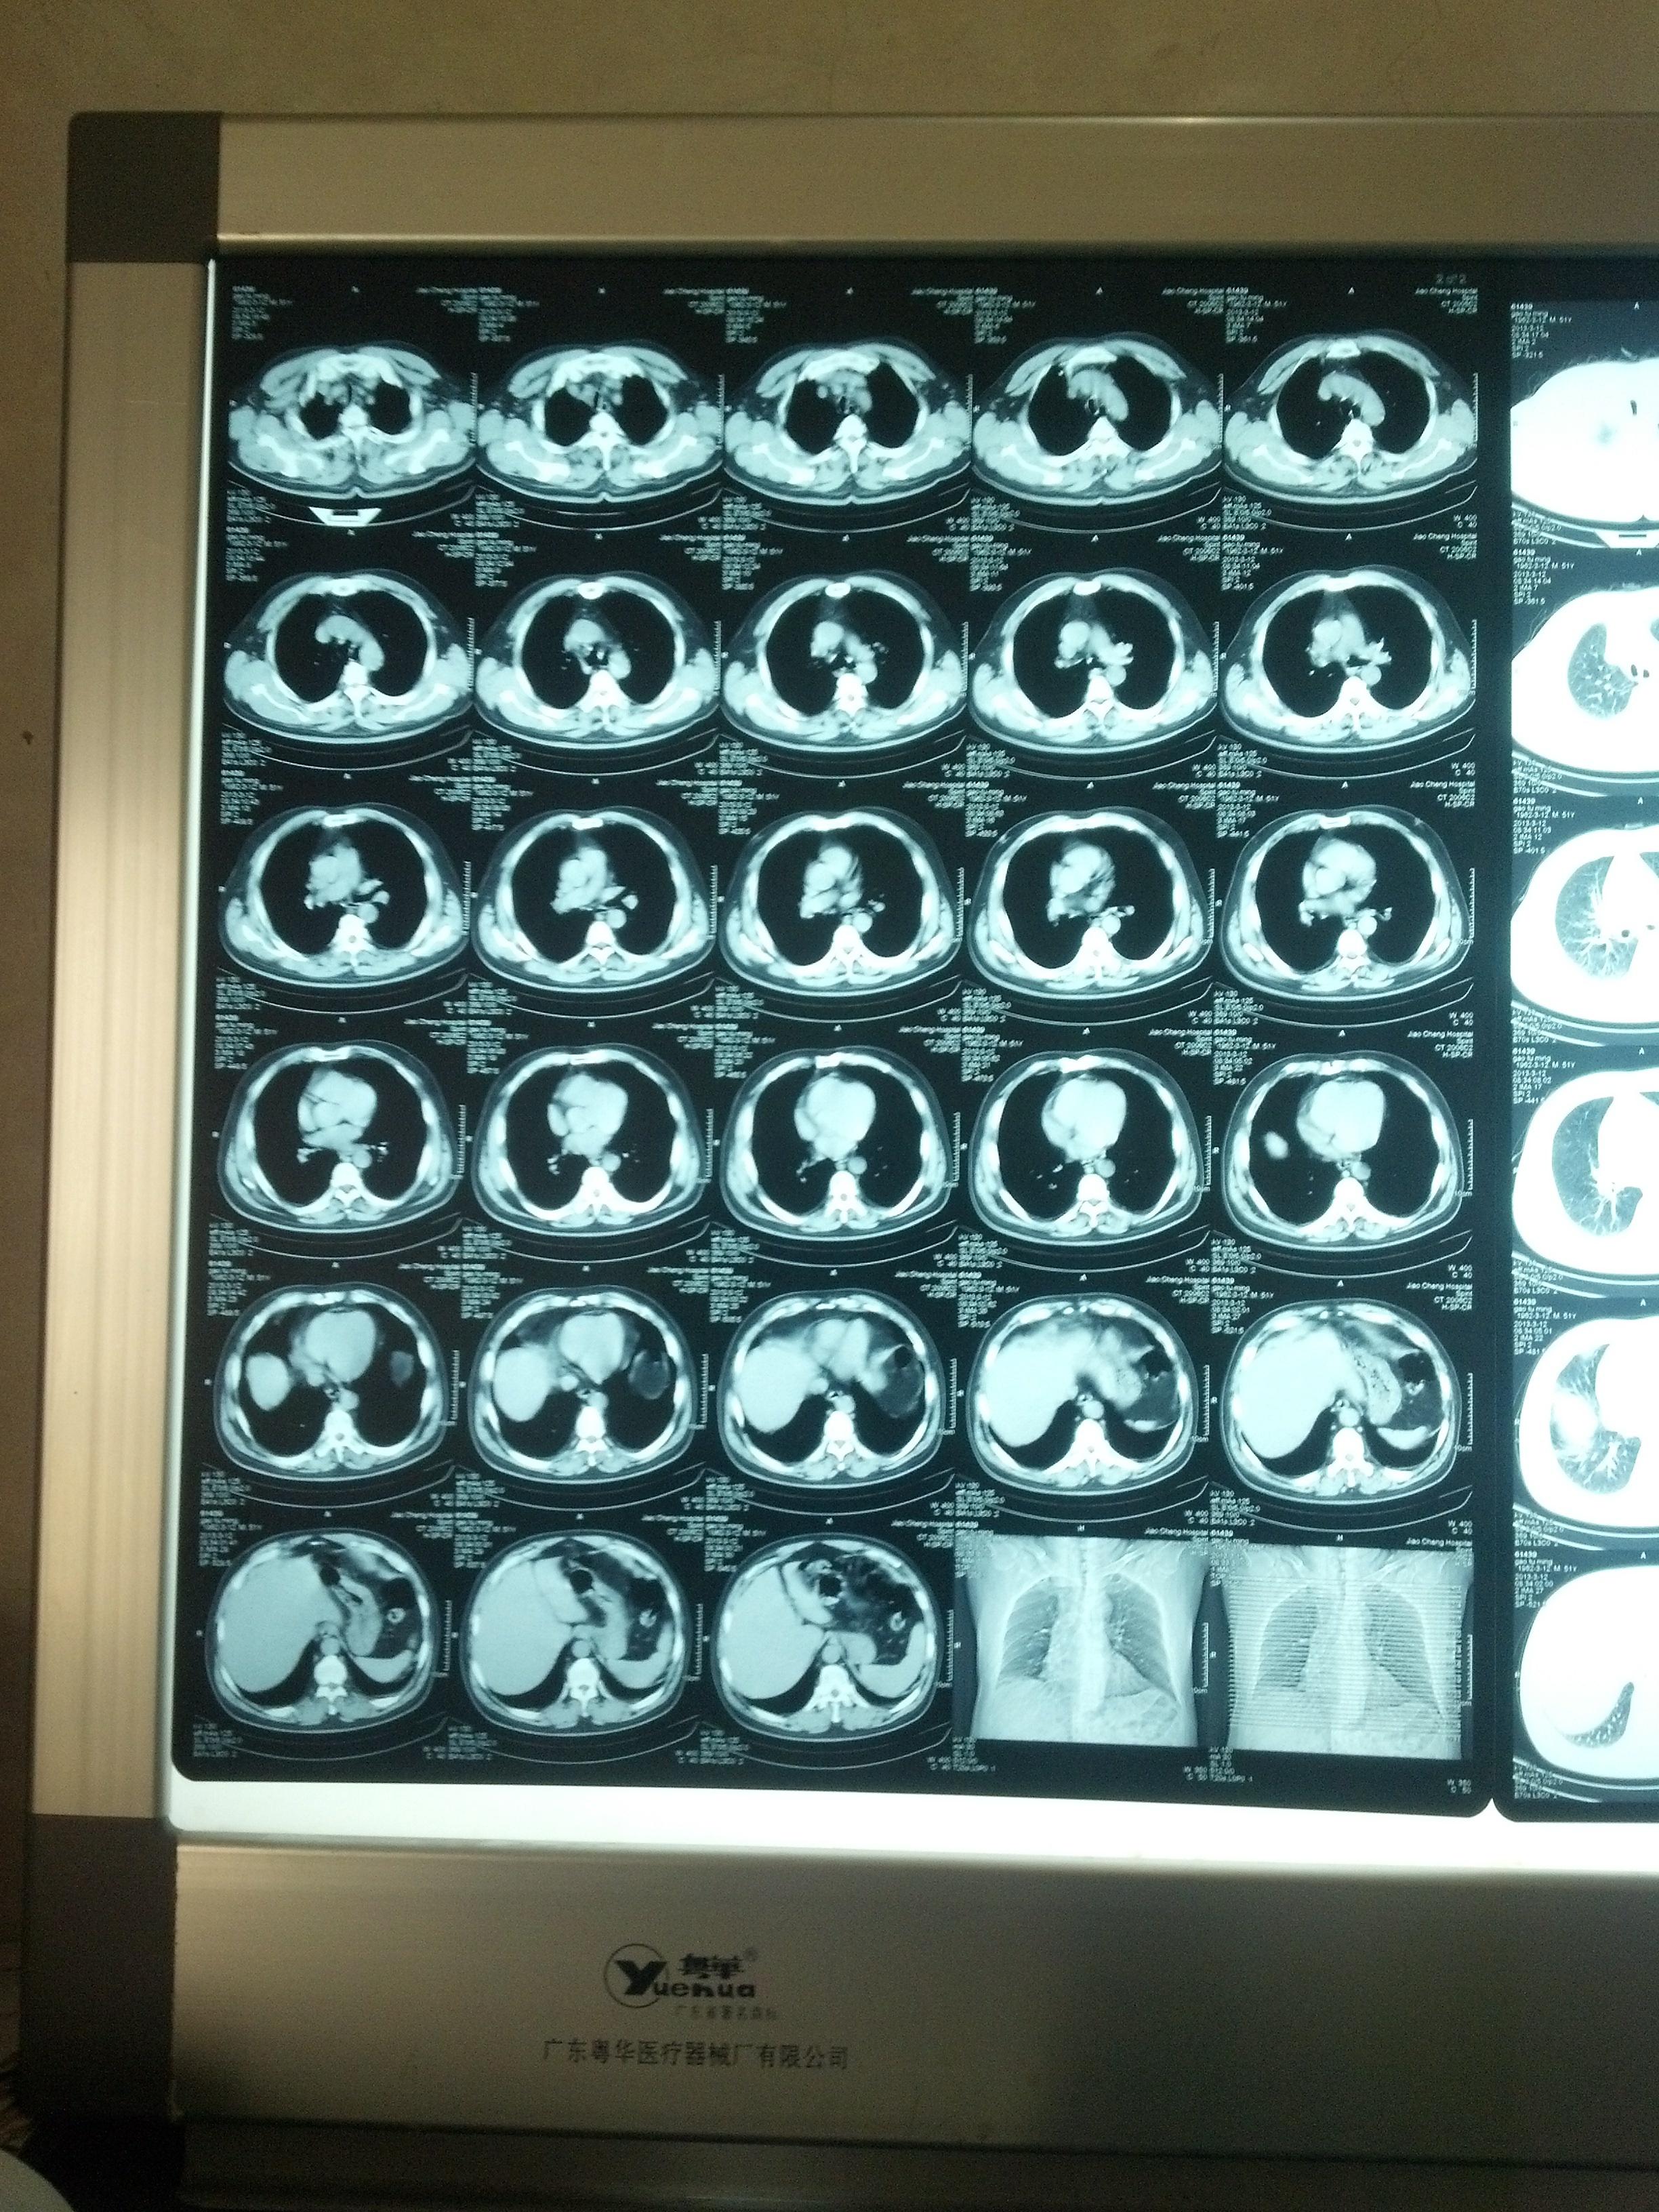

(介入前胸片可见纵膈增宽)

图片尺寸1600x1200